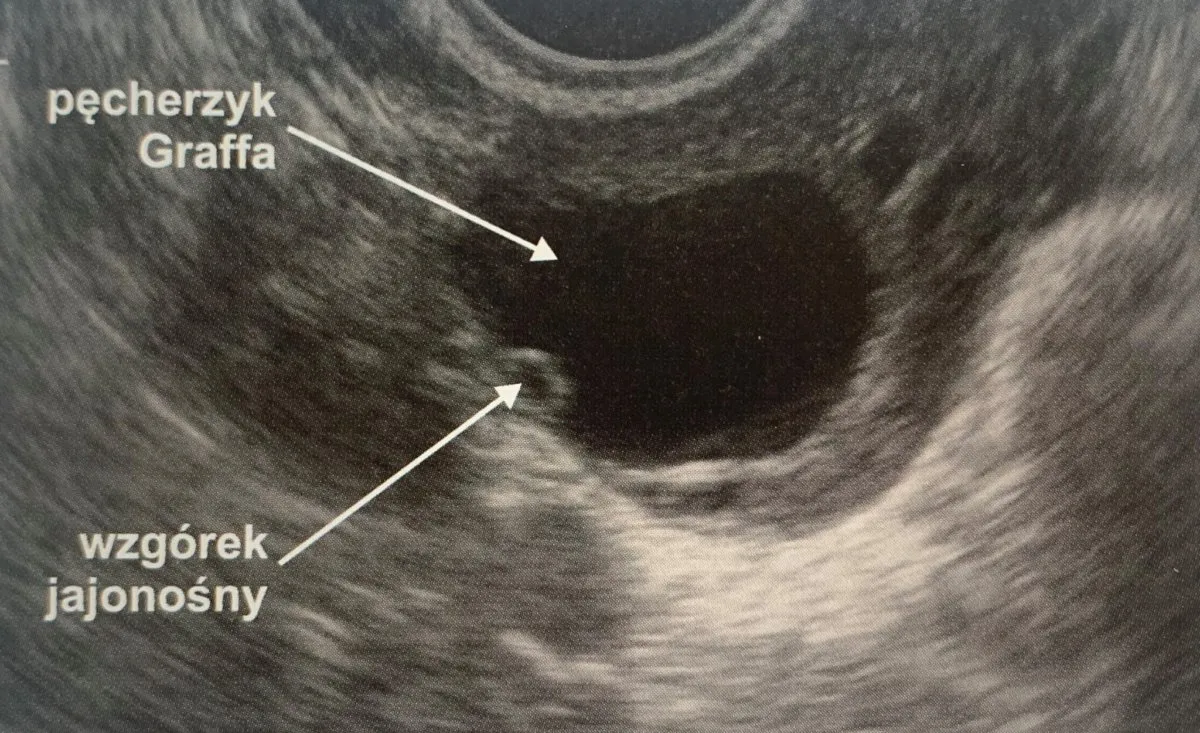

Przed owulacją w jajniku rozwija się jeden, dominujący pęcherzyk Graafa, który rośnie do imponujących rozmiarów, często osiągając 18-25 mm. Kiedy owulacja następuje, ten pęcherzyk pęka, uwalniając komórkę jajową. Dlatego pierwszym, bardzo wyraźnym sygnałem, który obserwuję w USG po owulacji, jest brak tego wcześniej widocznego, dużego pęcherzyka. W jego miejscu mogę dostrzec jedynie nieregularne, zapadnięte struktury pozostałości po pękniętym pęcherzyku, które wkrótce zaczną przekształcać się w ciałko żółte.

Znak nr 2: Pojawienie się "gwiazdy" poowulacyjnej ciałka żółtego